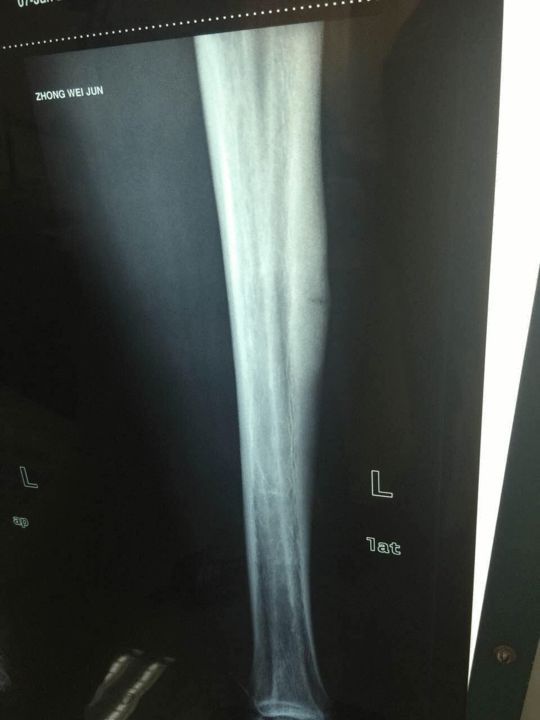

小腿胫骨疲劳性骨折了

看图说话胫骨疲劳性骨折